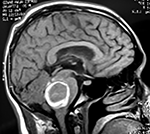

EJEMPLO DE CASO CLÍNICO (9)

Paciente masculino de 34 años de edad, quien presenta crisis convulsivas parciales motoras de brazo y hemicara derecha, secundariamente generalizadas, posteriormente hemiparesia 4/5 para hemicuerpo derecho.

La TAC muestra un área hiperdensa a nivel frontal izquierdo heterogénea que no refuerza con medio de contraste.

LA RMN muestra una lesión bien circunscrita frontal parasagital izquierda con edema perilesional, hiperintensa en T1 y T2, de contenido sólido y quístico, con poca captación del medio de contraste.

Se realizó craneotomía frontal para abordaje interhemisférico anterior.

Se realiza resección total de la lesión de contenido hemático oscuro-verdoso, consistente en un angioma cavernoso. La RMN postoperatoria se observa solo la brecha quirúrgica sin evidencia de lesión.

En el postquirúrgico el paciente desarrollo síndrome frontal lateral, que se controló con Risperidona y remitió después de tres semanas, las crisis convulsivas remitieron y el medicamento se disminuyó de manera paulatina (figs. 4 y 5).

Figura 4:

Imágenes prequirúrgicas y postquirúrgicas de lesión multiloculada del caso 9.